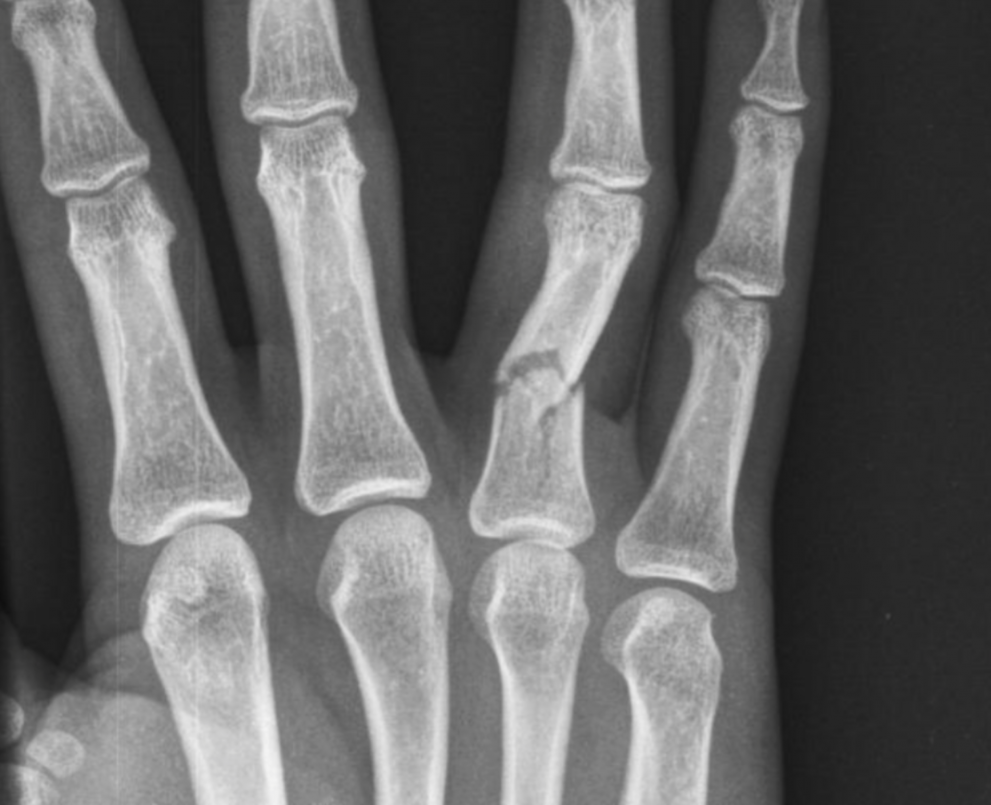

Vsaka od kosti na roki se lahko zlomi. Oblika zloma je odvisna od smeri in jakosti delovanja sile. Zlom je lahko enostaven (dva odlomka) ali zdrobljen (več odlomkov). Če je prisotna rana na koži je zlom odprt. Pri sklepnih zlomih lomna poka prečka sklepno površino. Zlomom so pridružene poškodbe mehkih tkiv.

Znaki zloma so bolečina, oteklina, modrica in zmanjšana gibljivost. Zardi sočasne poškodbe ali pritiska odlomkov na živce se lahko pojavi mravljinčenje ter odrevenelost. Večji premik odlomkov spremljata sprememba oblike ali prikrajšava prstov. Z rentgenskim slikanjem v dveh projekcijah zlom potrdimo in ga natančneje opredelimo.

Način zdravljenja je odvisen od vrste in mesta zloma ter pridruženih poškodb okolnih struktur. Cilj zdravljenja je čimboljša naravnava odlomkov, ki jih je potrebno zadržati v pravilnem položaju in omogočiti celjenje. Zlome brez ali z majhni premikom odlomkov zdravimo z mirovanjem v opornici ali mavcu. Enako zdravimo tudi zlome, ki jih naravnamo in pričakujemo, da se ob mirovanju ne bodo premaknili. Za učvrstitev zlomov lahko uporabimo tudi tanke žice, ki jih ob ustrezni anesteziji, z vrtalko uvedemo skozi kožo. Pri odprtih zlomih in zlomih, ki jih ne moremo naravnati ali zadržati v željenem položaju moramo prerezati kožo ter si zlom prikazati. Po naravnavi ga v pravilnem položaju zadržimo z vijaki, ploščicami ali žicami. Pri močno zdrobljenih zlomih uporabimo zunanji fiksater – ogrodje, ki učvrsti kostne odlomke preko žic, ki jih uvedemo skozi kožo. Za uspešno zdravljenje sklepnih zlomov je potrebno doseči čim boljše ujemanje sklepnih površin. Pri zlomih na roki je pomembno, da učvrstitev (osteosinteza) omogoča zgodnje razgibavanje, saj dolgotrajna imobilizacija vodi v slab funkcionalni rezultat.